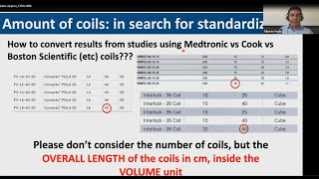

New Approach in Endoleak Type II Management

Prof. Gargiulo, Prof. Froio and Dr Mascoli discuss the predictive factors in indentifying high-risk patients as well as outcomes of routine sac embolisation in the patient population.